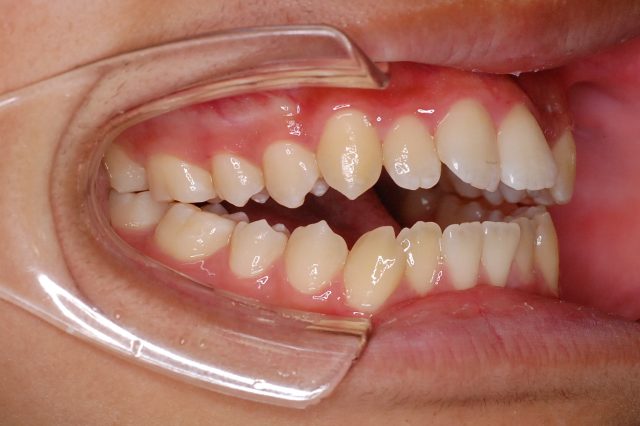

Before

After

主訴

前歯で噛めない

治療期間・回数

2年6ヶ月・30回

治療方法

マルチブラケットにて上下左右4本抜歯

費用

850000+税

デメリット・注意点

歯根吸収 歯肉退縮